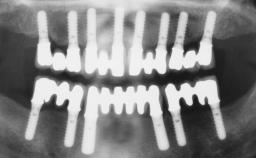

Immediate Loading of Six Implants in the Maxilla and Final Restoration with a Full-Arch CAD/CAM Zirconia FDP

# of Implants 6

Type of Implants One-Piece

Defining Characteristics Fully edentulous upper jaw to be rehabilitated with four or more implants

Modality 6+ implants with immediate loading